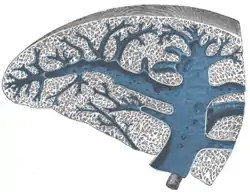

Pulp

Micrograph of splenic tissue showing the red pulp (red), white pulp (blue) and a thickened inflamed capsule (mostly pink – top of image). H&E stain.

The spleen contains two different tissues, white pulp (A) and red pulp (B). The white pulp functions in producing and growing immune and blood cells. The red pulp functions in filtering blood of antigens, microorganisms, and defective or worn-out red blood cells.

AreaFunctionComposition

red pulpMechanical filtration of red blood cells. In mice: Reserve of monocytes[5]

white pulpActive immune response through humoral and cell-mediated pathways.Composed of nodules, called Malpighian corpuscles. These are composed of: